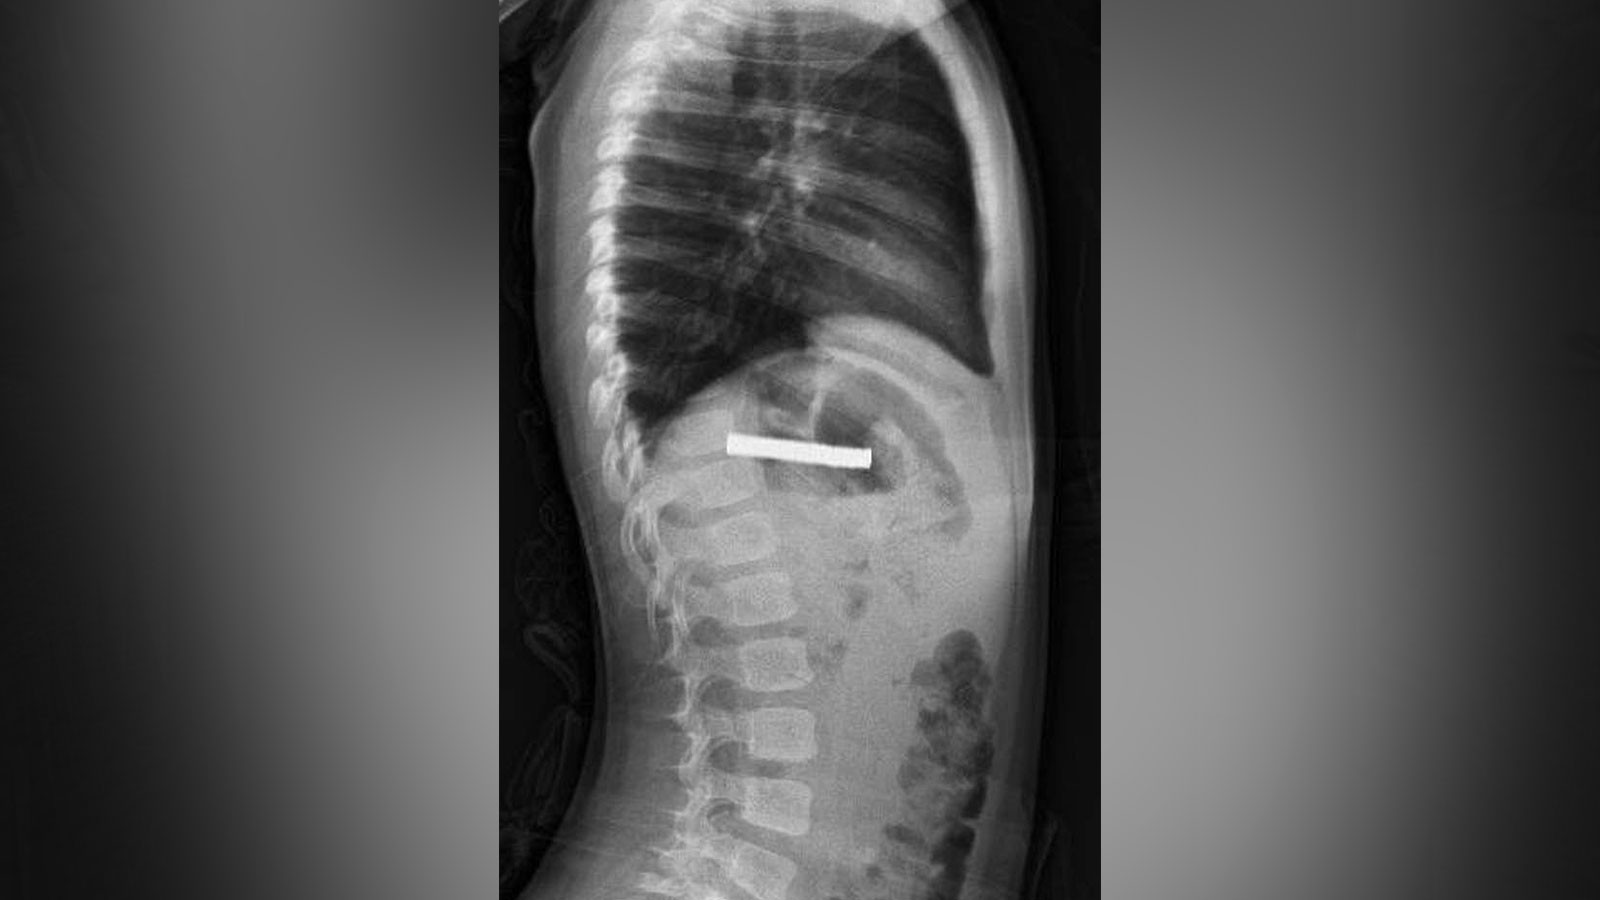

Elazığ’da 3 yaşındaki bir çocuğun 19 adet mıknatıs yuttuğu tespit edildi. Çocuğun yemek borusuna yapışan mıknatıslar, endoskopik yöntemle çıkarıldı.